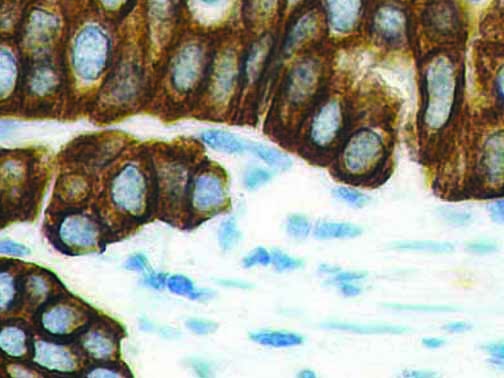

The first cytokines released are interleukin 1β (IL-1β) and tumor necrosis factor-α (TNF-α), which attract a variety of circulating white blood cells (WBCs) to the infection site, including neutrophils, monocytes, macrophages, and natural killer (NK) cells. This response, along with the antipathogenic chemicals released by these cells (i.e., complement), comprise the innate immune response. These cells directly attack the invading pathogen and also release additional cytokines, chief among them interleukin-1 and 6 (IL-6). IL-6 is essential for invoking the adaptive immune response, which calls T-cells, B-cells, and T helper (Th) cells to the infection site. IL-6 also stimulates further recruitment, proliferation and activation of macrophages.

It is the ICU physician who is most likely to witness one of the deadliest manifestations of the abnormal immunological response, the cytokine storm syndrome (CSS). This response is also referred to by some as the cytokine release syndrome (CRS). CSS is characterized by continuous activation and expansion of macrophage and lymphocyte populations, which secrete large amounts of cytokines, causing the cytokine storm. This massive cytokine release is akin to hemophagocytic lymphohistiocytosis (HLH) disease, a syndrome characterized by initial unchecked and persistent activation of cytotoxic T lymphocytes and NK cells.